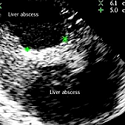

Two hepatic abscesses of biliary origin: interest of echography

Zine el Abidine Benali

PAMJ. 2013; 16: 151. Published 21 December 2013